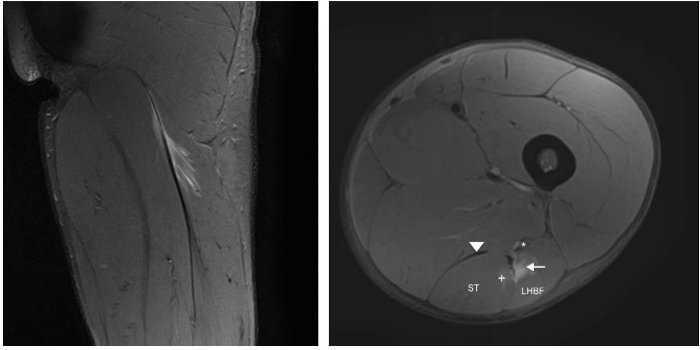

Un jugador de futbol professional de dinou anys patí un dolor sobtat a la regió posterior superior de la cuixa en esprintar que l’impedí jugar. Els senyals clínics mostraren una tibantor aguda dels isquiotibials (palpació dolorosa, rang de moviment [ROM] limitat, disminució de la força, estirament dolorós i dificultat per caminar normalment). Es practicà RM 24 hores després del traumatisme amb un escàner 3-T (Titan Vantage, Toshiba). La lesió i les característiques de CLBF es descriuen a les figures 1 i 2. El diagnòstic final fou una lesió proximal UMT de CLBF localitzada a 10 cm de la tuberositat isquial i a 6 cm des de l’inici d’UMT. El temps de baixa previst fou de 7-8 setmanes. El tractament de recuperació consistí bàsicament en 3 fases: fisioteràpia, entrenament de força i neuromuscular al gimnàs i entrenament individual específic de futbol al camp.

Un jugador de futbol professional de divuit anys sofrí el mateix tipus de dolor en les mateixes circumstàncies. Els senyals clínics eren totalment similars als del cas dels isquiotibials aguts descrit, però la prova d’RM mostrà imatges diferents (figs. 3 i 4) perquè la lesió estava localitzada al tendó lliure del bíceps femoral. La longitud del tendó lliure fou 8,5 cm i la lesió fou localitzada a 6,5 cm de la tuberositat isquiàtica. Degut al llarg període de recuperació i a un índex elevat de relesió, cal considerar el tractament quirúrgic. Es realitzà l’escissió del teixit cicatricial, incloent-hi el trencament parcial del tendó y la sutura sense tensió del romanent del ventre del bíceps femoral al semitendinós adjacent, amb la finalitat de proporcionar tensió al tendó i reforç amb ancoratge a la tuberositat isquiàtica (figs. 3 i 4).